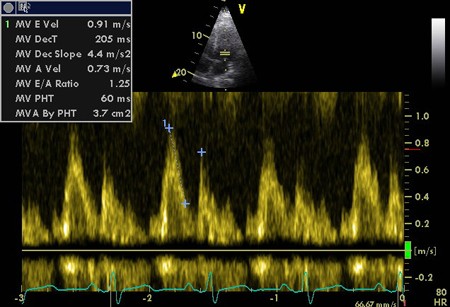

Pseudonormalização de fluxo de entrada mitral do E:A

Do acervo de Dr Jessica Webb; usado com permissão